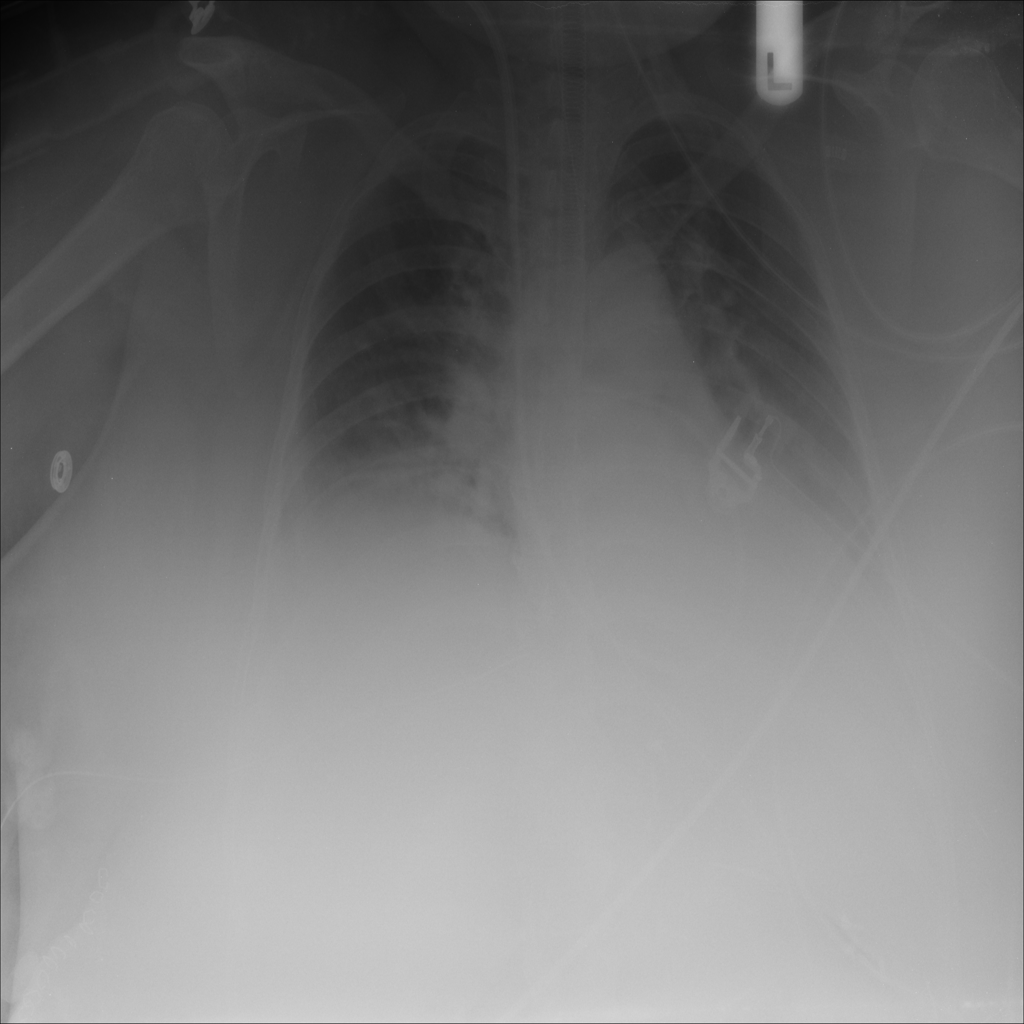

PAT-3384 · IMG-054Atelectasis

PAT-3384 · IMG-054

AP